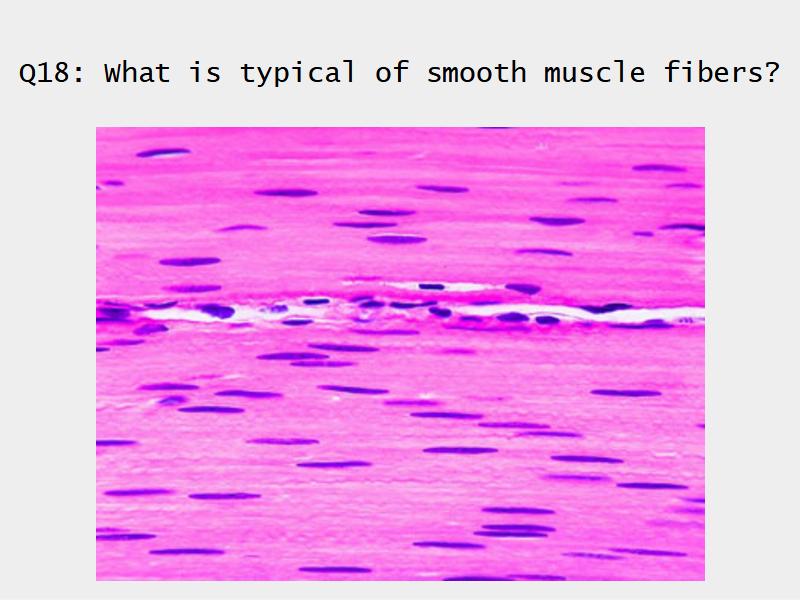

- Smooth muscle REPLACE cartilage

- Smooth muscle